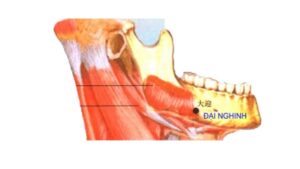

2. Vị trí huyệt Đại Nghênh

Xưa: trước xương quai hàm 1.3 th, trước chỗ hõm của xương nơi có động mạch.(huyệt Giá Xa ra hía trước 5 phân).

Nay: Cắn chặt răng lại, huyệt ở sát bờ trước cơ cắn và trên bờ dưới xương hàm dưới, ngang một khoát ngón tay, ngay trên rãnh động mạch mặt.

Giải Phẫu : Dưới da là bờ dưới cơ cười, cơ mút, sát bờ trước cơ cắn, rãnh động mạch mặt của xương hàm dưới.